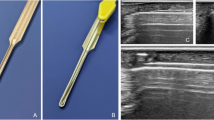

Needle release

Like the thread release, before the procedure, the relevant anatomical structures were visualized using ultrasound. The needle (18-gauge × 40 mm, BD Nokor™ Admix needle, Becton, Dickinson and Company, USA) was inserted distally to the ligament with the sharp side facing the A1 pulley. Hydrodissection (injection of fluid to separate the A1P from the surrounding structures) was performed to separate the A1P from the flexor tendon (Video 1). Depending on the size of the finger, approximately 2-3 ml of saline was injected. In patients with trigger finger, even less volume could potentially be used due to the swollen annular ligaments with often seen surrounding soft tissue edema due to inflammation. Since this study was conducted on cadavers, only saline was utilized to simulate saline containing 1% or 2% lidocaine, as suggested by Guo et al. [20]. The application of preoperative local anesthetic was not simulated in this study. After confirming the correct position, the transection was performed by back-and-forth movement, using the needle as a knife (Figs. 1, 2,Video 2).